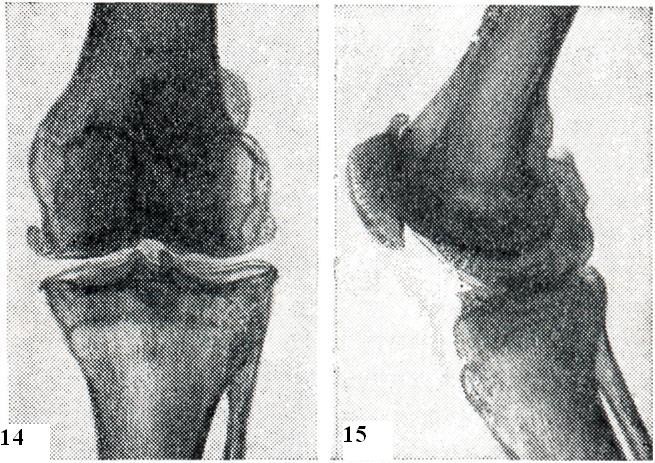

Рис. 14 и 15. Артроз коленного сустава (III стадия).

Рис. 14.

Сушение суставной щели, краевые остеофиты (рентгенограмма, прямая проекция).

Рис. 15.

Сушение щели мешду надколенником и бедренной костью, остеофиты на верхнем и нишнем краях надколенника (рентгенограмма, боковая проекция).

На рентгенограммах коленных суставов (рис. 14 и 15) характерные для артроза изменения: сужение суставной щели, подхрящевой склероз, краевые остеофиты и кистовидная перестройка прилегающих частей костей.

К числу ранних рентгенологических признаков гонартроза относятся заострения межмыщелковых бугорков болынеберцовой кости. Наблюдаются также мелкие эрозии в нижней трети задней поверхности надколенника, сужение щели между надколенником и бедренной костью и остеофиты на верхнем и нижнем краях надколенника. При гонартрозе часто поражаются суставные мениски, особенно медиальный. Это приводит к резкому сужению суставной щели или к О-образной или Х-образной деформациям.